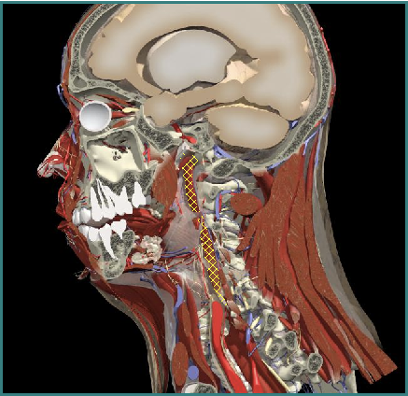

Torticaput

Cervical Dystonia

Muscle Selection

Muscles Attaching to Skull

- Ipsilateral rotation

Splenius capitis

Splenius cervicis

Longissimus capitis

Obliquis capitis inferior

Levator Scapulae

Contralateral rotation

Trapezius

Sternomastoid

Semispinalis capitis

Spinalis capitis